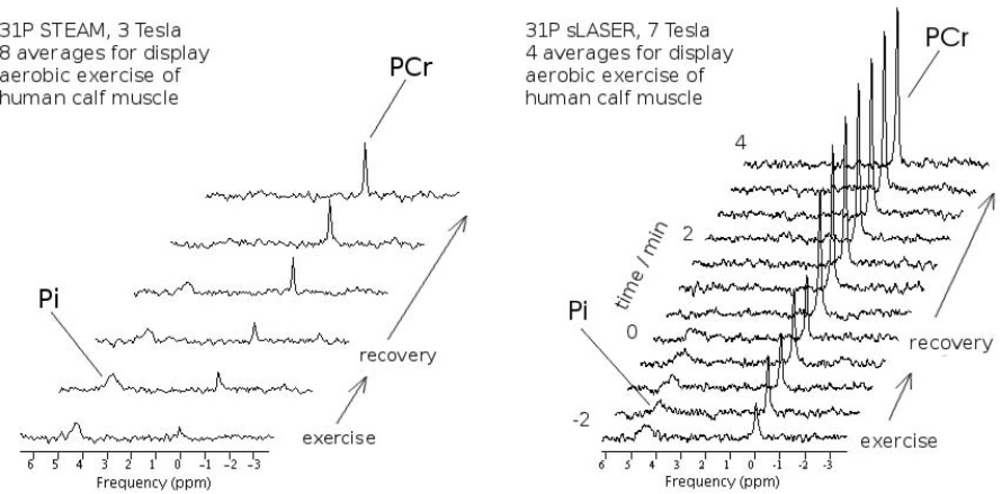

- Meyerspeer, M.; Scheenen, T.; Moser, E. Dynamic 31P MRS of exercising human muscle in a 7 T whole body system, with STEAM and semi-LASER localisation. Proc. Intl. Soc. Mag. Reson. Med (ISMRM), 17th Annual Meeting; 2009. # 2590.. [Google Scholar]

- Meyerspeer, M.; Krssak, M.; Kemp, G.J.; Roden, M.; Moser, E. Dynamic interleaved 1H/31P STEAM MRS at 3 Tesla using a pneumatic force-controlled plantar flexion exercise rig. Magn. Reson. Mater. Phy 2005, 18, 257–262. [Google Scholar]

- Meyerspeer, M.; Krssak, M.; Moser, E. Relaxation Times of 31P-Metabolites in Human Calf Muscle at 3 Tesla. Magn. Reson. Med 2003, 49, 620–625. [Google Scholar]

- Bogner, W.; Chmelik, M.; Schmid, A.I.; Moser, E.; Trattnig, S.; Gruber, S. Assessment of 31P relaxation times in the human calf muscle: a comparison between 3 T and 7 T in vivo. Magn. Reson. Med 2009, 62, 574–582. [Google Scholar]